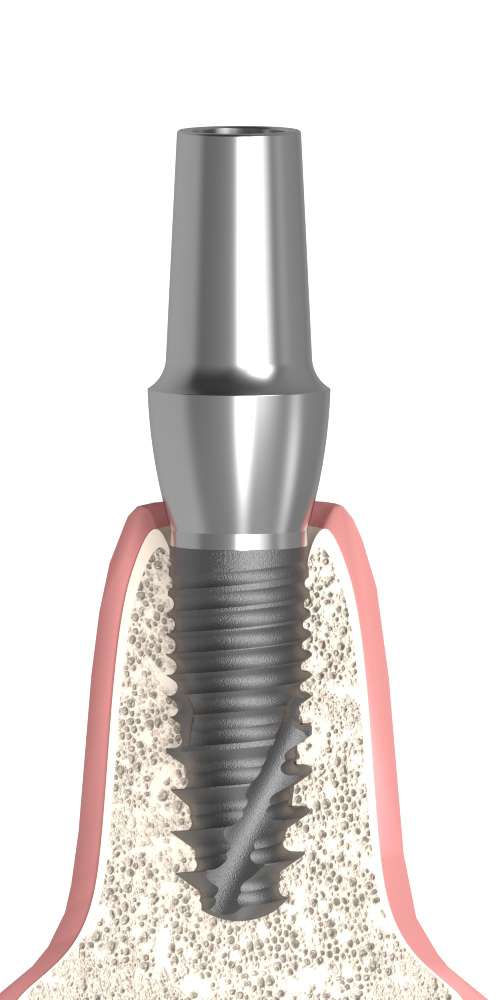

Anatomically Shaped, Customisable Abutment for Implants with Indexed Orientation

The Anatomic abutment, straight, positioned is an implant-level, customisable (grindable) abutment designed to follow the natural tooth shape, facilitating the creation of aesthetically pleasing and functional prosthetic restorations. Its preformed anatomical contour requires less grinding while still allowing for individual adjustment during the clinical or laboratory procedure.

The indexed design ensures that the abutment is always repositioned in the same orientation, which is essential in multi-implant restorations or anterior aesthetic zone reconstructions, where the uniform fit of soft tissue contours and crown shapes is critical.

- Anatomical shape: Preformed abutment supports the creation of a natural-looking restoration.

- Straight design: Ideal when the prosthetic axis is aligned with or close to the implant axis.

- Indexed orientation: Fixed positioning ensures accurate re-insertion and alignment.

- Implant-level connection: Stable, direct fit to the implant.

- Biocompatible titanium: Sterilisable, durable and tissue-friendly material for long-term clinical use.

The product image is for illustration purposes only. The colour and geometry of the product may vary depending on the selected size.